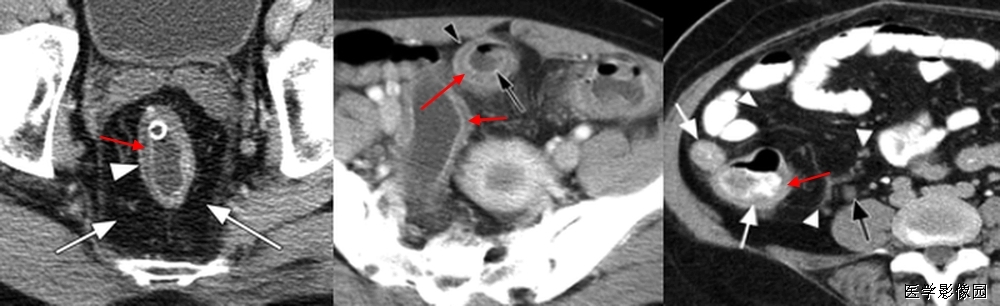

9、高密度环征

高密度环征是指在压痛部位结肠旁可见与结肠壁相连的肿块,近似于乳腺密度,中心密度较低,边缘密度较高,邻近脂肪间隙模糊,局部腹膜增厚。此为炎症导致增厚的脏层腹膜。组织病理显示致病的肠脂垂外脏层腹膜覆盖纤维白细胞渗出物。肠脂垂见于腹水CT。肠脂垂因扭转或自发性静脉血栓而梗死,继发炎症反应,称为原发性肠脂垂炎,区别于因周围器官病变导致的继发肠脂垂炎。

原发性肠脂垂炎的影像表现具有特异性,可以明确诊断。CT显示结肠周围1-4cm的脂肪密度团块周围2-3mm高衰减环。偶尔有高衰减中心,此为栓塞的血管及出血坏死。鉴别诊断包括继发肠脂垂炎和网膜梗死。结肠憩室炎是继发肠脂垂炎最常见的原因,需通过有无临近憩室、结肠壁增厚脓肿除外,多普勒超声有助于炎症和梗死的区别。网膜梗死常更大(3.5-7cm),蛋糕状,预后与原发性肠脂垂炎相。

肠脂垂附于结肠带,特别是沿独立带和网膜带的两侧,多见于盲肠和乙状结肠,为许多大小不等、形状不定的脂肪小突起,它是由肠壁浆膜下的脂肪组织集聚而成。每个肠脂垂通过一个狭窄的短蒂供血,这个带蒂的特点及较大的活动性大大增加了扭转及梗死机率,从而导致局部缺血引起炎症和四周水肿。

由于脂垂分部广泛,患病部位可自盲肠至乙状结肠,疼痛部位亦随之变化,压痛最明显的部位即病变脂垂所在部位,重者可有反跳痛及肌紧张,较少见,不易与急性阑尾炎、乙状结肠憩窒炎及某些妇科疾病相鉴别。当发现阑尾炎症状与体征不相符的患者时,经过CT检查,发现较典型的影像学表现,即可考虑到本病的存在。 因为好发于下腹,临床常诊断结肠憩室炎和阑尾炎原发性肠脂垂炎是自限性疾病,一般1周后自动缓解,因此明确诊断很重要,可以避免不必要的手术和临床处理。

左图:腹部增强CT横扫显示结肠附近高衰减环(箭头)围绕脂肪密度中心。此环为肠脂垂炎症导致外脏层腹膜增厚。

右图:CT显示结肠周围1-4cm的脂肪密度团块周围2-3mm高衰减环。偶尔有高衰减中心,此为栓塞的血管及出血坏死。

结肠旁与结肠壁相连肿块,近似于乳腺密度,中心密度较低,边缘密度较高,邻近脂肪间隙模糊,局部腹膜增厚